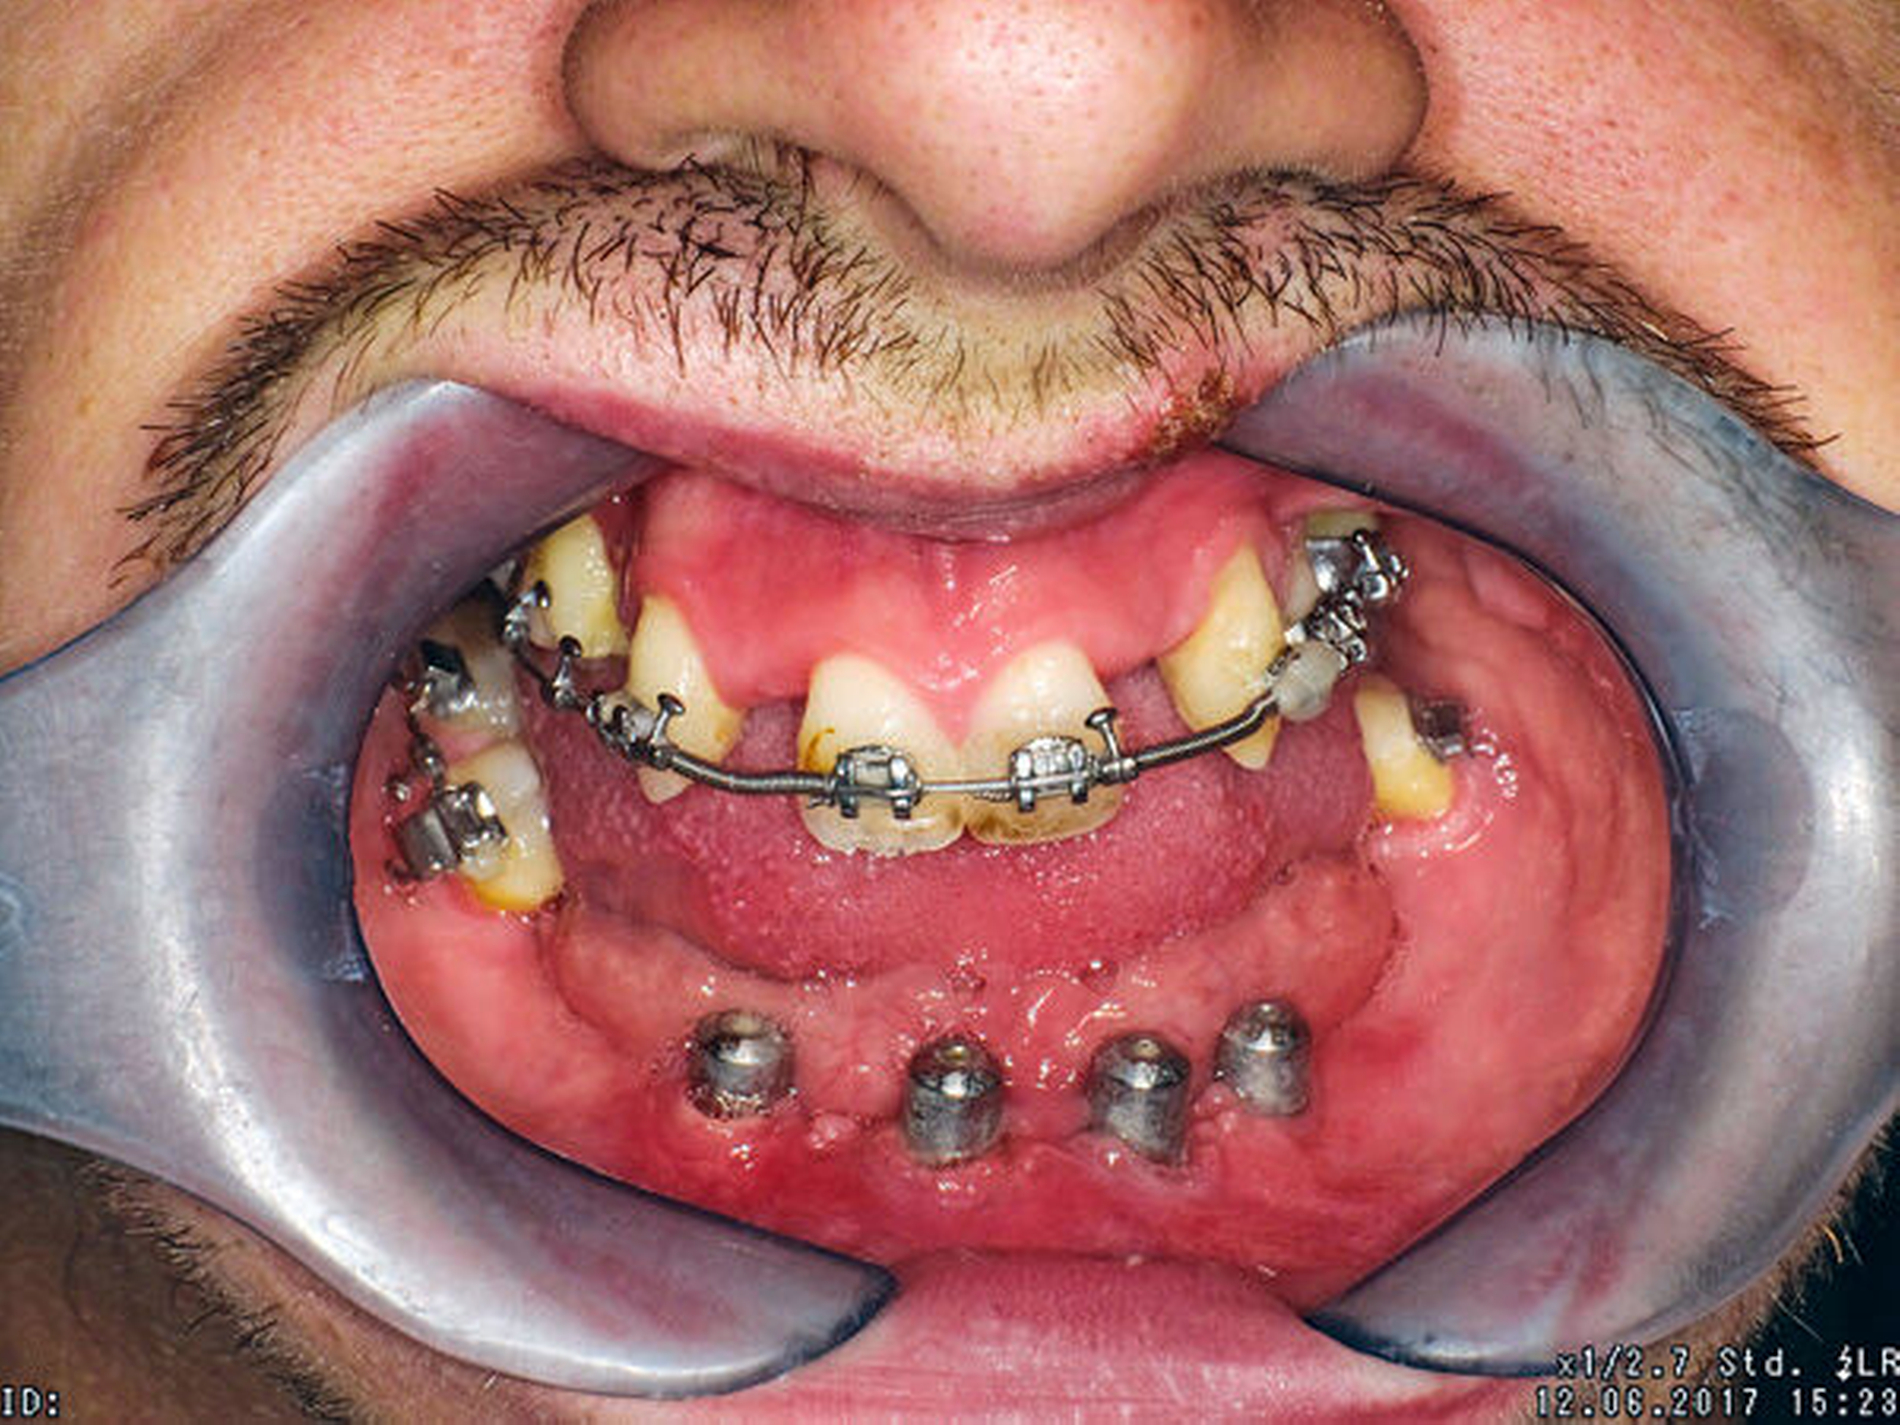

Vor der prothetischen Rehabilitation war dementsprechend eine kieferorthopädische und kieferchirurgische Vorbehandlung mit dem Ziel der dreidimensionalen skelettalen und dentalen Harmonisierung zwingend indiziert. Zunächst wurden die kariös zerstörten Zähne 14, 22 und 36 sowie die verlagerten Zähne 24 und 38 entfernt. Im Oberkiefer wurde eine kieferorthopädische Therapie eingeleitet, um den Zahnbogen auszuformen. Hierbei wurde eine Lückenöffnung in den Regiones 012 und 022 mit Protrusion der Zähne 11 und 21 vorgenommen. Im Anschluss konnte schließlich im Unterkiefer eine interforaminäre Insertion von vier Implantaten erfolgen (Abbildung 4).

Anschließend wurde eine bimaxilläre Umstellungsoperation (in der Le-Fort-I-Ebene und nach Obwegeser/Dal Pont) durchgeführt (Abbildung 5). Hierfür wurde für den OP-Splint eine provisorische Implantat-getragene Prothese im Unterkiefer angefertigt, so dass die Implantate letztlich auch zur Eingliederung des OP-Splints dienten (Abbildungen 6 und 7). Zusätzlich konnte postoperativ durch die Implantat-getragene Prothese die Okklusion gesichert und das Risiko eines Rezidivs im Sinne einer Okklusionsverschiebung minimiert werden [Ohba et al., 2015].